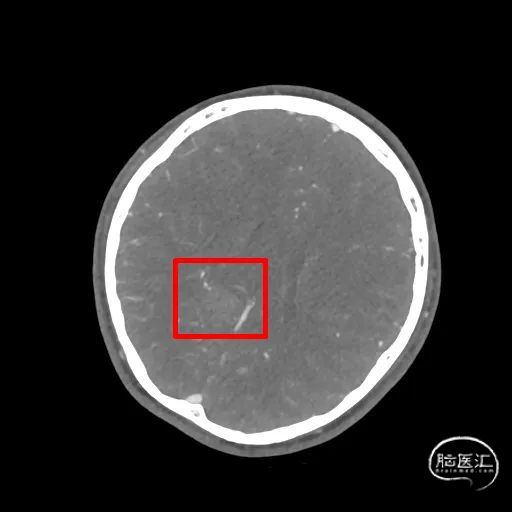

图1. 头部CT及CTA提示:右侧半卵圆区-侧脑室旁血肿,右侧血肿旁局部小动脉血管稍增粗,血管畸形待排。